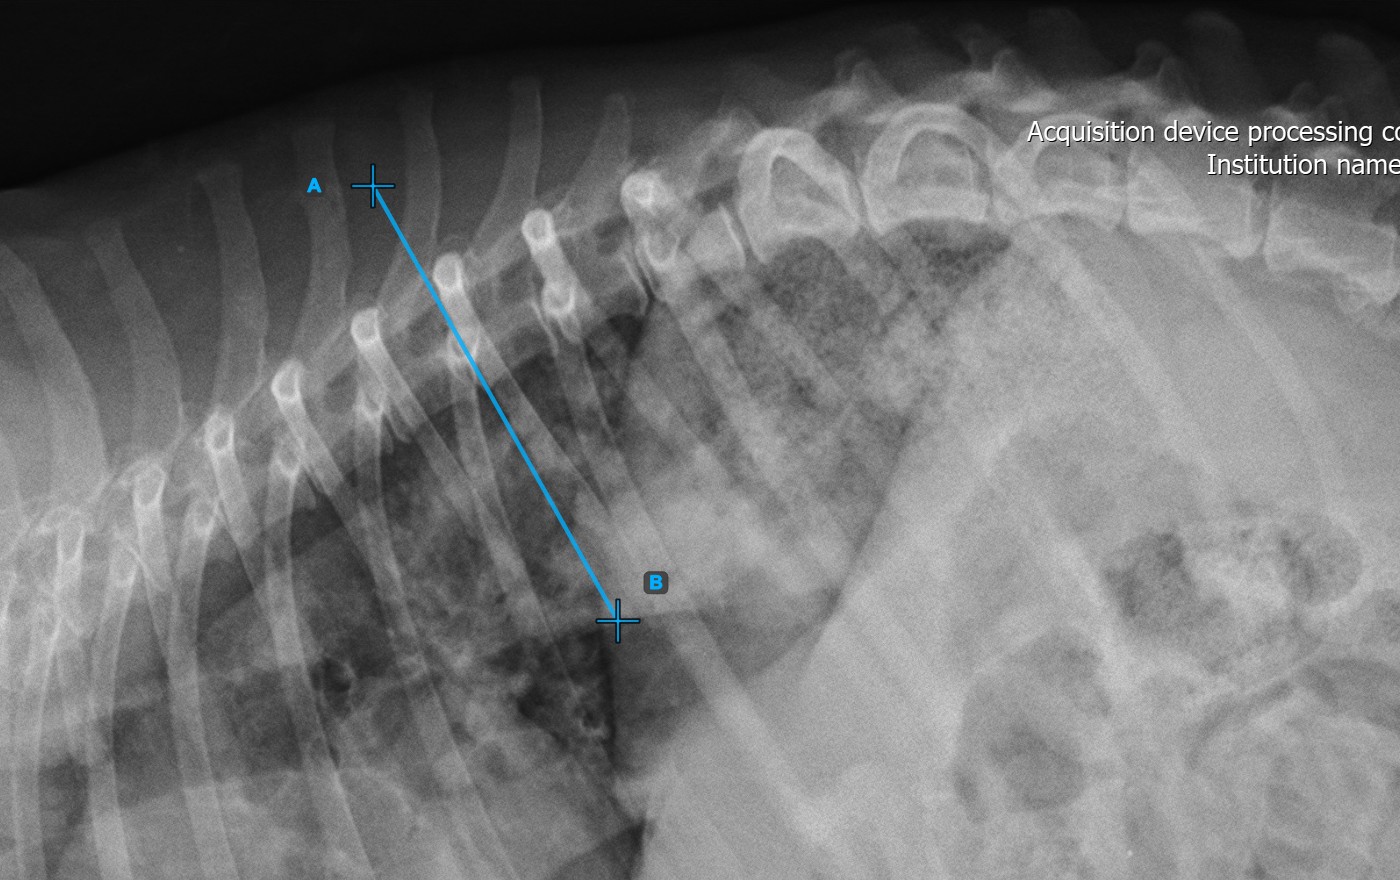

Start the measurement by marking the first vertebral line on the spine.

Identify the vertebral endplate at the initial point of the largest spinal curve deformity. Place the start and end point of the first vertebral line precisely along the identified endplate. Adjust each point on the scene to better align the line with the endplate if needed.

The image below represents a typical placement of the first vertebral line.